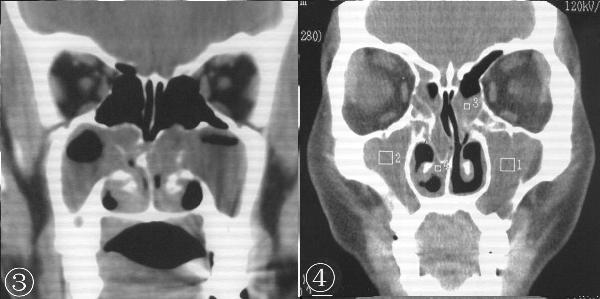

得了鼻息肉就要手术吗?不手术可以吗?这个就需要视患者的具体病情而定了。我院在检查方面配备了内窥镜以及CT设备,视野良好,准确度高,可以清晰看见患者鼻内鼻息肉的具体状况,查明病因,以便确定后期治疗方案。

鼻息肉CT图片